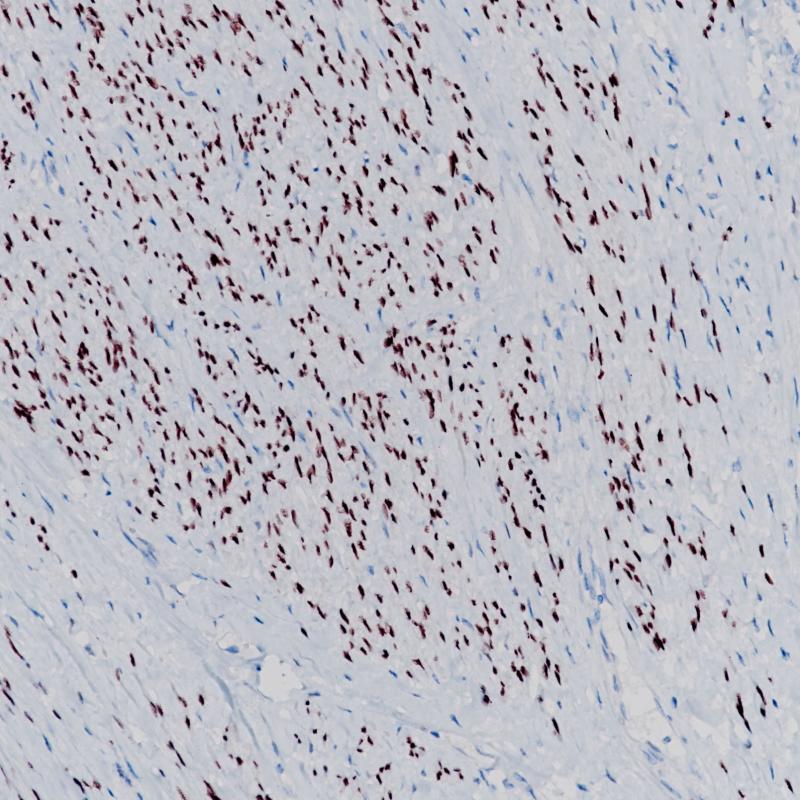

In normal epithelia, nuclear WT1 expression is largely restricted to ovary (surface epithelium and inclusion cysts) and fallopian tube, while WT1 is not found in endometrial or cervical epithelium. As regards nonepithelial cells, nuclear WT1 is found in mesothelium and some submesothelial stromal cells, stromal cells of the female genital tract, testicular non-germinal cells, and kidney (podocytes). In tumor tissues, WT1 is detected in tumor cells of Wilms’ Tumor (also known as nephroblastoma) and mesothelioma. Additionally, WT1 expression has been found in ovarian serous carcinomas and some breast carcinomas.WT1 is particularly used for distinguishing malignant mesothelioma and ovarian serous carcinoma from nonserous carcinomas. As for malignant mesothelioma, calretinin and WT1 are superior to cytokeratin 5/6, N-cadherin and thrombomodulin. WT1 is also applicable for the differential diagnostic of small cell childhood tumours.

WT1 Recombinant Rabbit Monoclonal Antibody